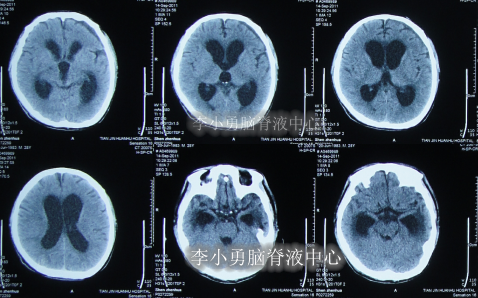

患者于2011年6月20日,因意外车祸致全身多器官损伤昏迷,当天住入天津著名的三甲脑科医院,检查明确颅脑外伤、肺挫伤、骨盆骨折(片子丢失),头部MRI和CT提示颅骨骨折,脑干弥漫性轴索损伤,颅内有出血,水肿(图-1、图-2)。

图-1:2011年6月20日头部MRI

图-2:2011年6月20日头部CT